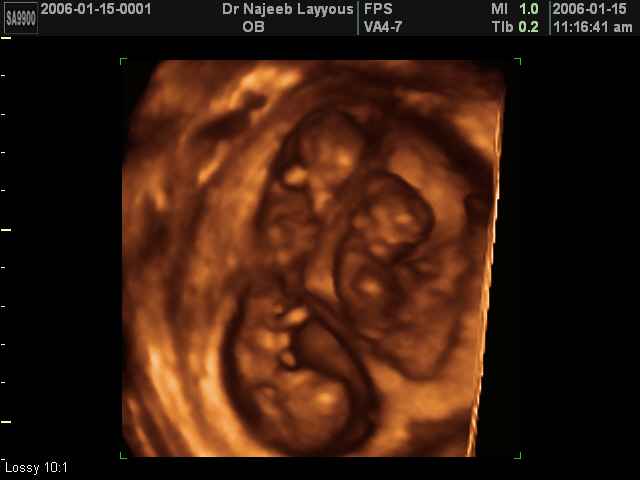

شوفوا صور التراساوند حقت التوينز

هنا حمل توينز عمره 5اسابيع

اجنة توام عمرهم سبع اسابيع

اجنة توام عمرهم 11 اسبوع